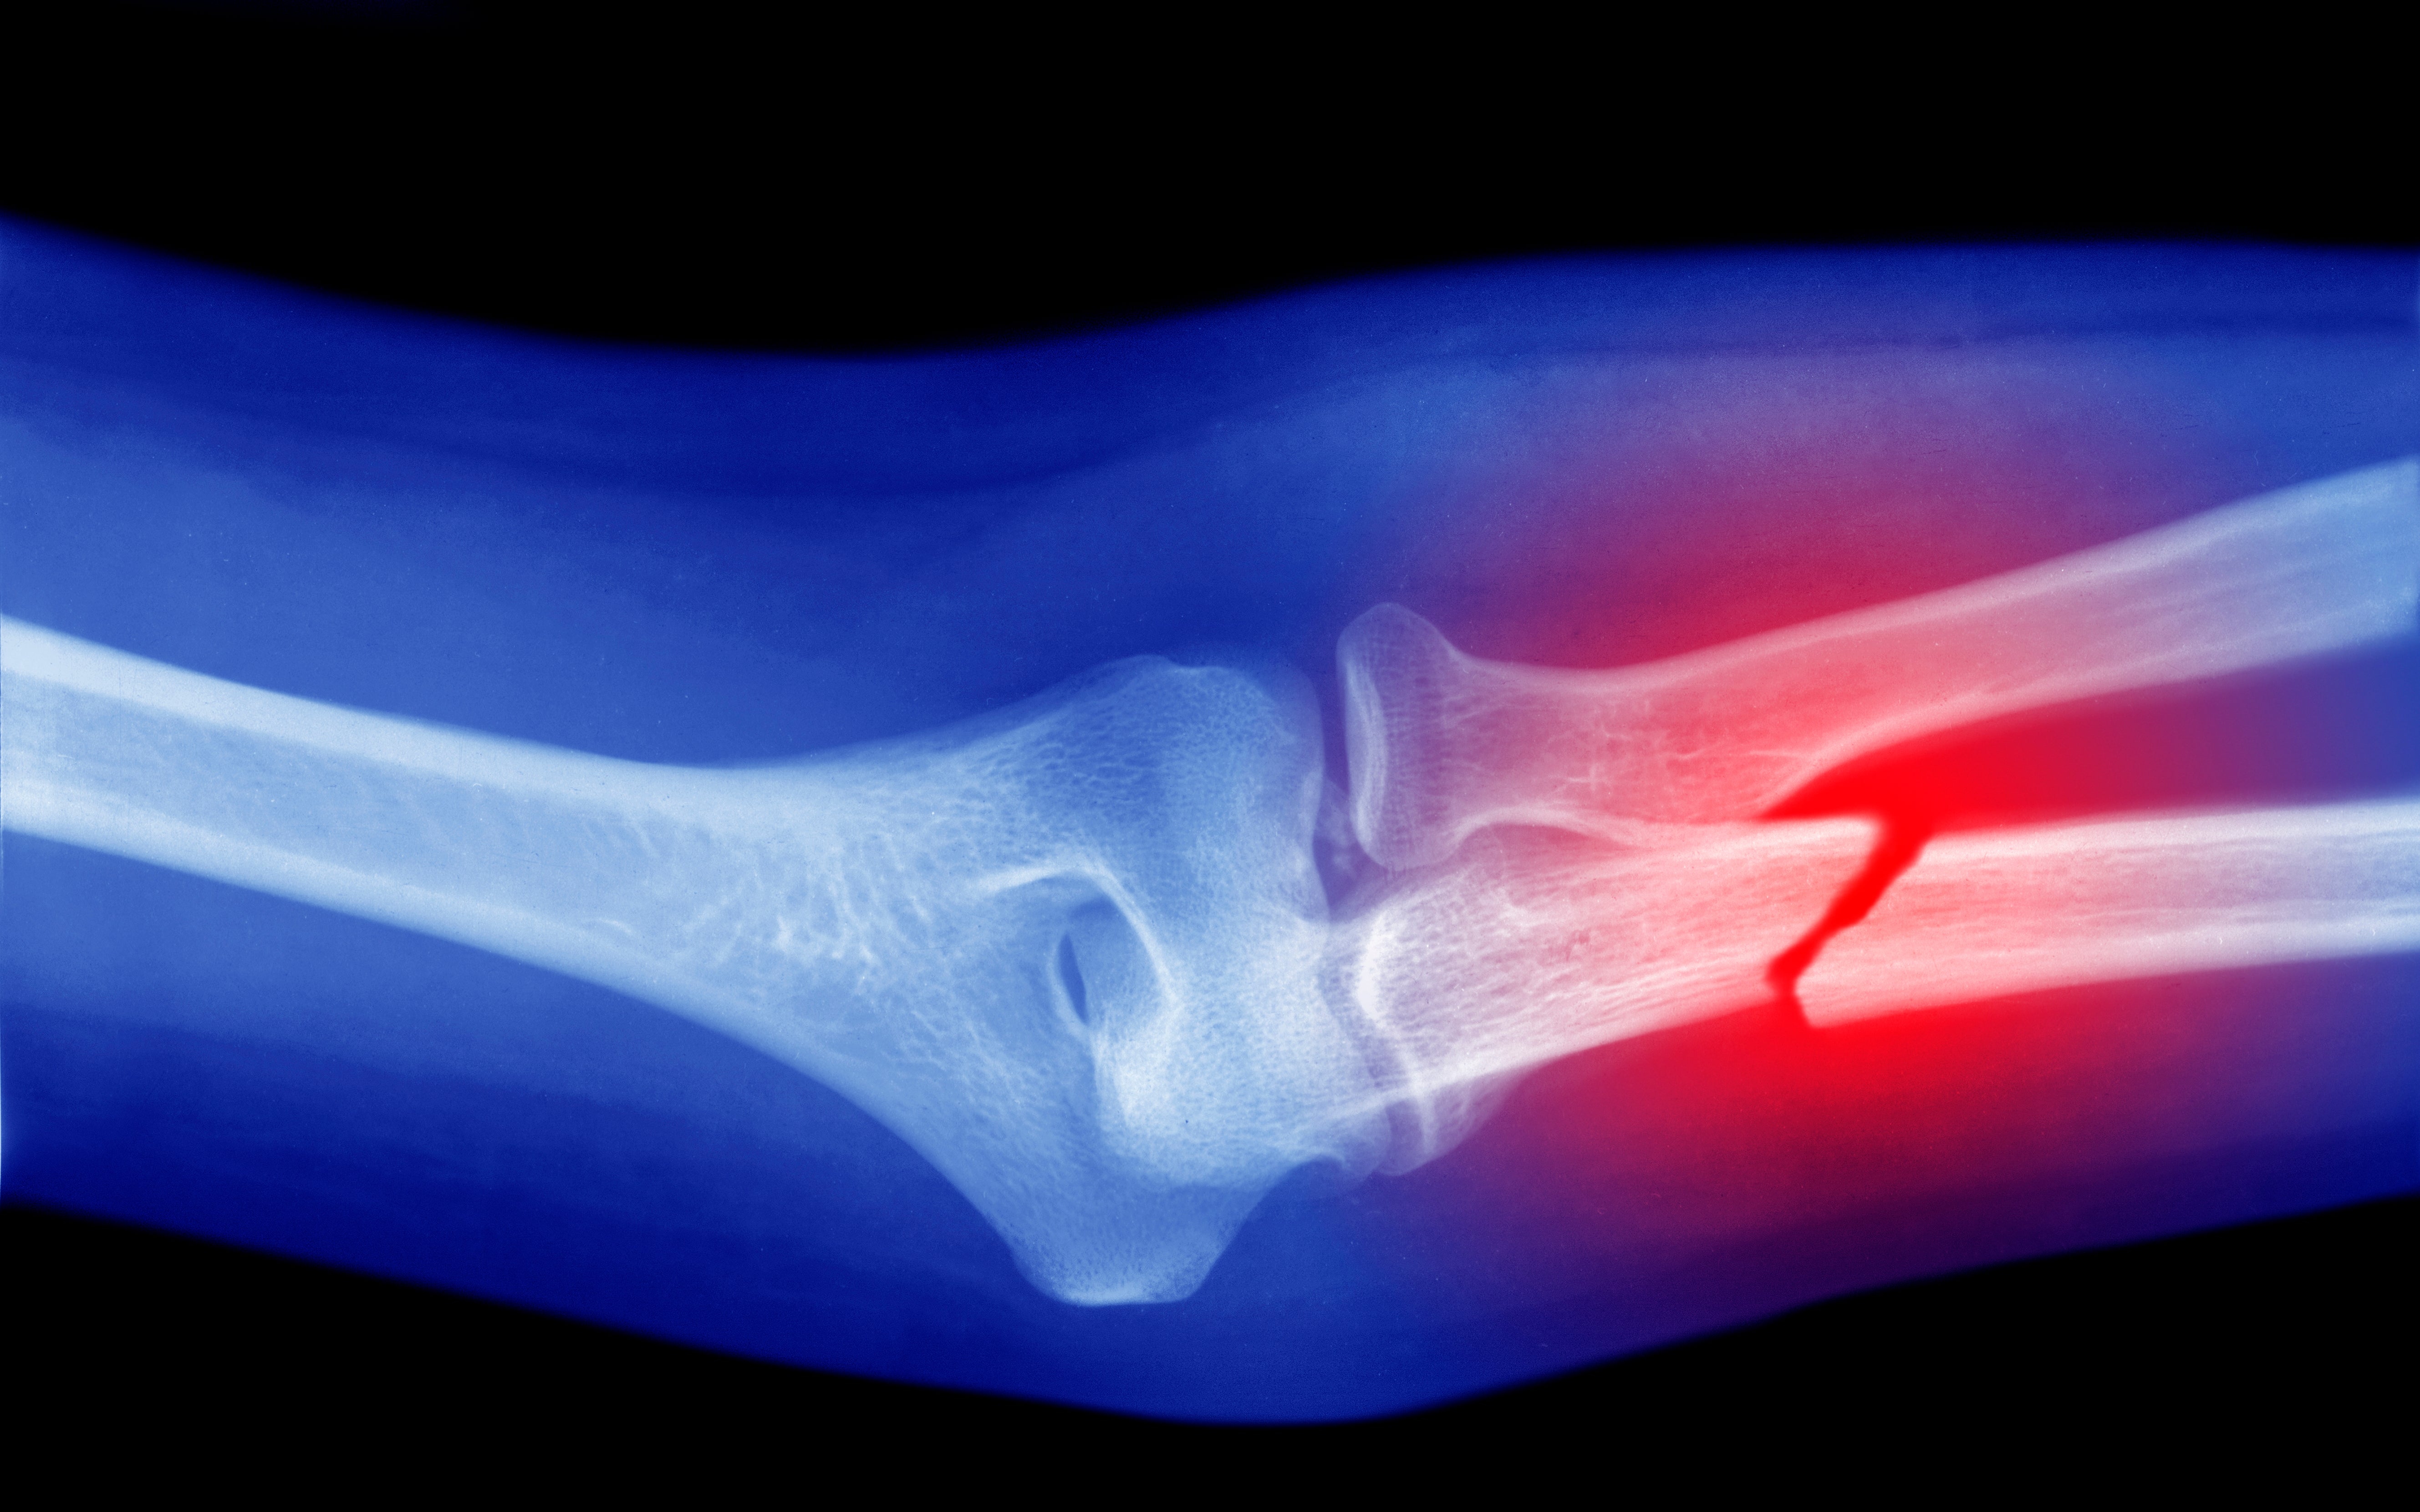

Vibration hilft Knochen beim Wachsen. In einer neuen Studie haben Forschende gezeigt, wie solche mechanischen Reize die Gene in den Knochen beeinflussen. Damit wollen sie künftig gebrochene Knochen schneller heilen. Die im Wissenschaftsmagazin "Science" veröffentlichten Studienergebnisse könnten die Grundlage für Therapieansätze gegen Knochenbrüche und Knochenschwund bilden, teilte die Eidgenössische Technische Hochschule Zürich (ETH Zürich) am Montag mit.

Für die neue Studie erstellten die Forschenden daher einen Atlas der Genaktivität in heilenden Mäuseknochen. Dazu brachen sie vier Mäusen einen Oberschenkelknochen, wie aus der Studie hervorgeht. Die Heilung der Knochen unterstützten sie mit einer Vibrationstherapie. Für jeden Punkt im Knochen bestimmten sie, welche Gene während der Heilung aktiv waren und welche nicht.

So konnten sie zeigen, dass bestimmte Gene spezifisch in den Bereichen des Knochens aktiv waren, die mechanisch stark belastet wurden. Umgekehrt waren Gene, die die Knochenbildung hemmen, an diesen Stellen nicht aktiv.

Die Forschenden wollen diese Erkenntnisse nun nutzen, um neue Therapieansätze zu finden. Denkbar wäre laut der ETH Zürich neben einer Vibrationstherapie auch ein gezielter Einsatz von Medikamenten, die gewünschte Gene aktivieren oder hemmen.